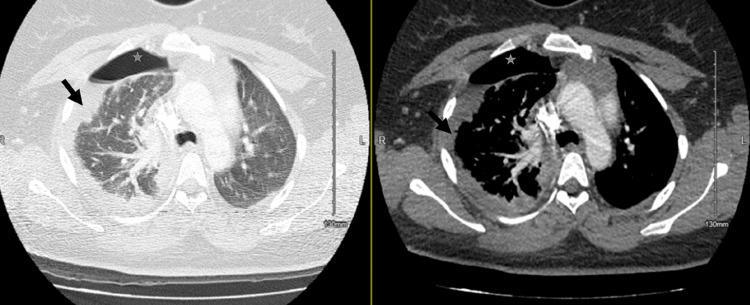

Community-acquired pneumonia is a leading cause of death from infectious diseases globally. Parapneumonic effusion is one of the most common complications of community-acquired pneumonia. As the infection progresses within the pleural space, loculation and empyema may develop. In rare cases, the parapneumonic effusions can progress significantly within 24 hours, which has been described as explosive pleuritis and may confer additional morbidity. Group A is the leading causative microorganism, which in itself has higher rates of parapneumonic effusions. We describe the case of a 30-year-old-female with a past medical history of asthma who presented to the emergency department with a sore throat, cough, and runny nose and was discharged on the same day after treatment of asthma exacerbation with upper respiratory tract infection. She re-presented within 24 hours with shortness of breath and right-sided pleuritic chest pain. Chest x-ray showed a new, large right-sided pleural effusion for which pleural fluid culture grew group A . She ultimately had prolonged hospitalization, requiring chest tube placement, and video-assisted thoracoscopic surgery (VATS). VATS was unsuccessful and she was treated with long-term antibiotics. This case demonstrates the dramatic evolution of explosive pleuritis and highlights the typical challenges encountered in these cases.

社区获得性肺炎是全球感染性疾病导致死亡的主要原因之一。类肺炎性胸腔积液是社区获得性肺炎最常见的并发症之一。随着感染在胸腔内进展,可出现分隔和脓胸。在罕见情况下,类肺炎性胸腔积液可在24小时内显著进展,这被描述为暴发性胸膜炎,可能会带来额外的发病率。A组是主要的致病微生物,其本身导致类肺炎性胸腔积液的发生率较高。我们描述了一名30岁女性的病例,她有哮喘病史,因咽痛、咳嗽和流涕到急诊科就诊,在治疗哮喘急性加重合并上呼吸道感染后于当天出院。她在24小时内再次就诊,出现气短和右侧胸膜炎性胸痛。胸部X线显示右侧有新的大量胸腔积液,胸腔积液培养生长出A组 。她最终住院时间延长,需要放置胸管,并接受了电视辅助胸腔镜手术(VATS)。VATS手术未成功,她接受了长期抗生素治疗。该病例展示了暴发性胸膜炎的急剧演变,并突出了这些病例中遇到的典型挑战。